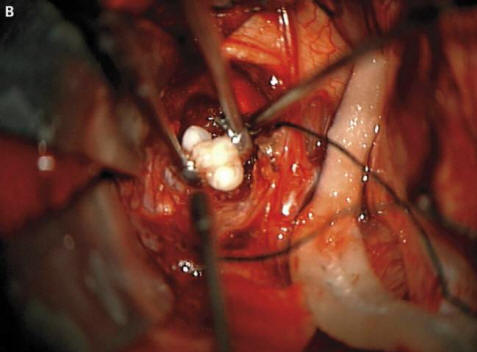

foto da fonti aperte Come spiegavano i chirurghi ai genitori spaventati e gli oncologi, questo era dovuto alla formazione di un raro congenito tumori – craniofaringiomi, scrive il New England Journal of Medicine. Questa neoplasia nella stragrande maggioranza dei casi benigno, tuttavia, può crescere fino alle dimensioni di una palla per golf e provoca una diminuzione del senso dell’olfatto, dell’udito e della vista alterati e aumenta anche la pressione intracranica. Ricercatori sempre sospettavo che questi tumori che compaiono in un bambino già nel gravidanza, formata dalle stesse cellule dei denti, dal momento che hanno rilevato grandi accumuli di calcio, ma un vero dente formato prima di questo caso non riescono a trovare rappresentato.

I chirurghi hanno rimosso con successo la foto da fonti aperte Il tumore, il ragazzo, dicevano, sta bene. Comunque un dente che è cresciuto nella sua ghiandola pituitaria, ma ha distrutto il cervello, in particolare, corretta produzione di ormoni: il paziente dovrà assumerli prima fine vita. Questo caso può legittimamente essere al primo posto un elenco delle operazioni più strane eseguite dagli oncologi. Nel frattempo, in giovane iraniano, che doveva trattare gli occhi pelosi. Uno strano tumore nei suoi occhi apparve quasi subito dopo la nascita, tuttavia all’età di 19 anni è aumentato significativamente in dimensioni (fino a 0,6 cm) e impedito la chiusura delle palpebre, inoltre, da esso i capelli rigidi hanno iniziato a crescere. I medici hanno rimosso il tumore e l’hanno scoperto questo è un dermoide limbale – estremamente raro, di solito educazione benigna. Secondo i medici, in quel caso, se il giovane continuava a tirare con le medicine, il suo gonfiore potrebbe non solo far crescere i capelli, ma anche iniziare a sudare: nel tempo sulle neoplasie compaiono spesso le ghiandole corrispondenti.